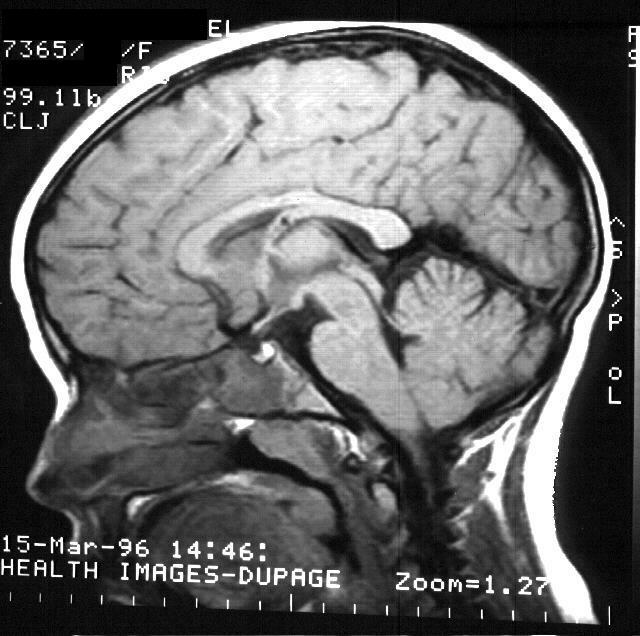

A lot of things can cause seizures, including infection, drugs, metabolic disorders, medications, disorder in blood vessels, or bleeding inside the brain. I am, by no means, a doctor (yet) but I can hypothesize that it was either due to the shot that he recieved or the fever that he had before due to an infection.